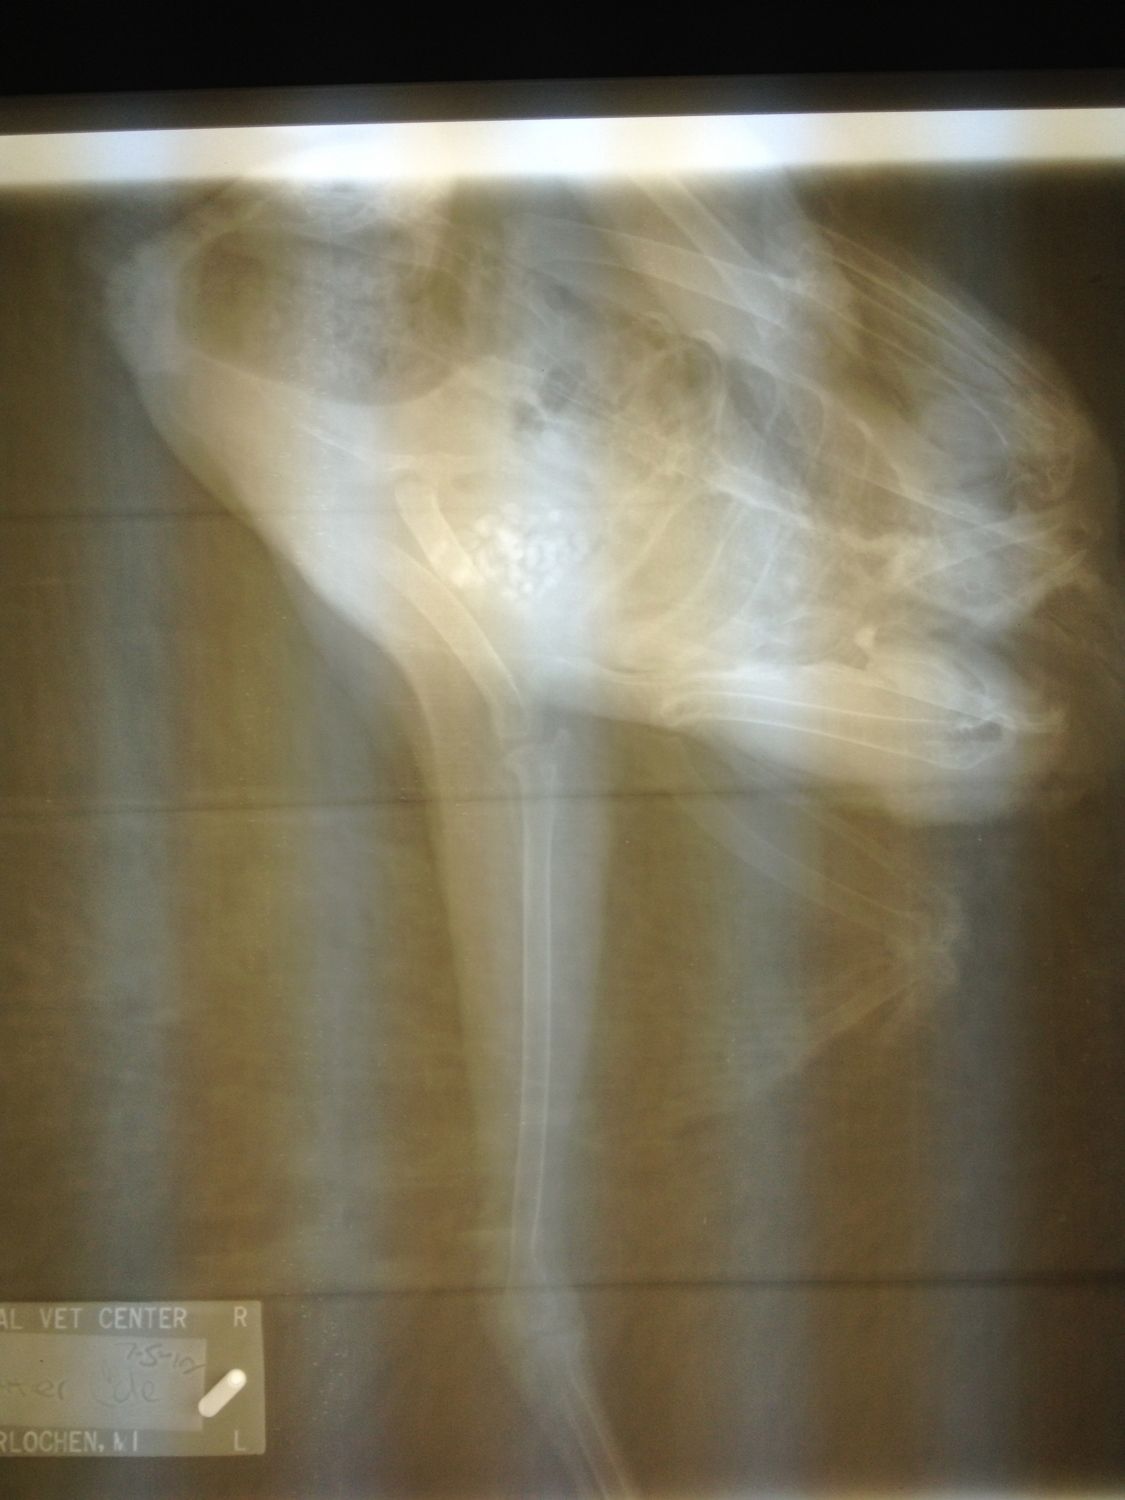

Well it's official...she broke her leg. The vet was extremely nice and took a lot of time with Peanut Butter. She said short of surgery which she didn't recommend PB will heal but most likely have a gimpy walk when all is said and done. So she's all bandaged up and doing fine. Hopefully in 6-8 weeks she can return to the flock. It seems that although she's eating she has lost quite a bit of weight. Any ideas on how to fatten her back up?

Let me know if you need any other angles. It's not overly tight and gives her just enough give to be able to hobble around a little. She put some weight on it for the first time today in a week! And I agree that Flock Mistress rocks!